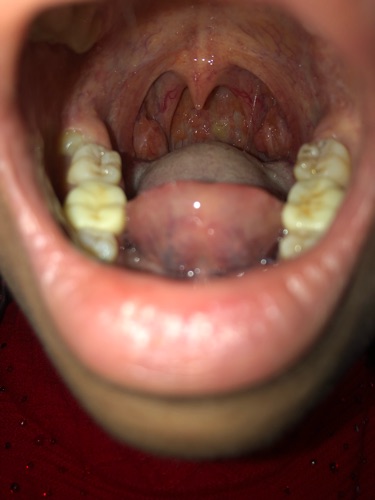

Bs thấy 2 amygdal em to; sung huyết. Tuy nhiên việc khạc ho ra dây máu có khá nhiều nguyên nhân như nguyên nhân tổn thương ở hầu họng; nguyên nhân ở phổi; nguyên nhân đường dẫn khí; ... Bs cần hỏi em thêm một số triệu chứng nữa để tư vấn cẩn thận cho em rồi kê đơn. Nếu em có thời gian em đặt lịch khám bs để trao đổi cụ thể nhé